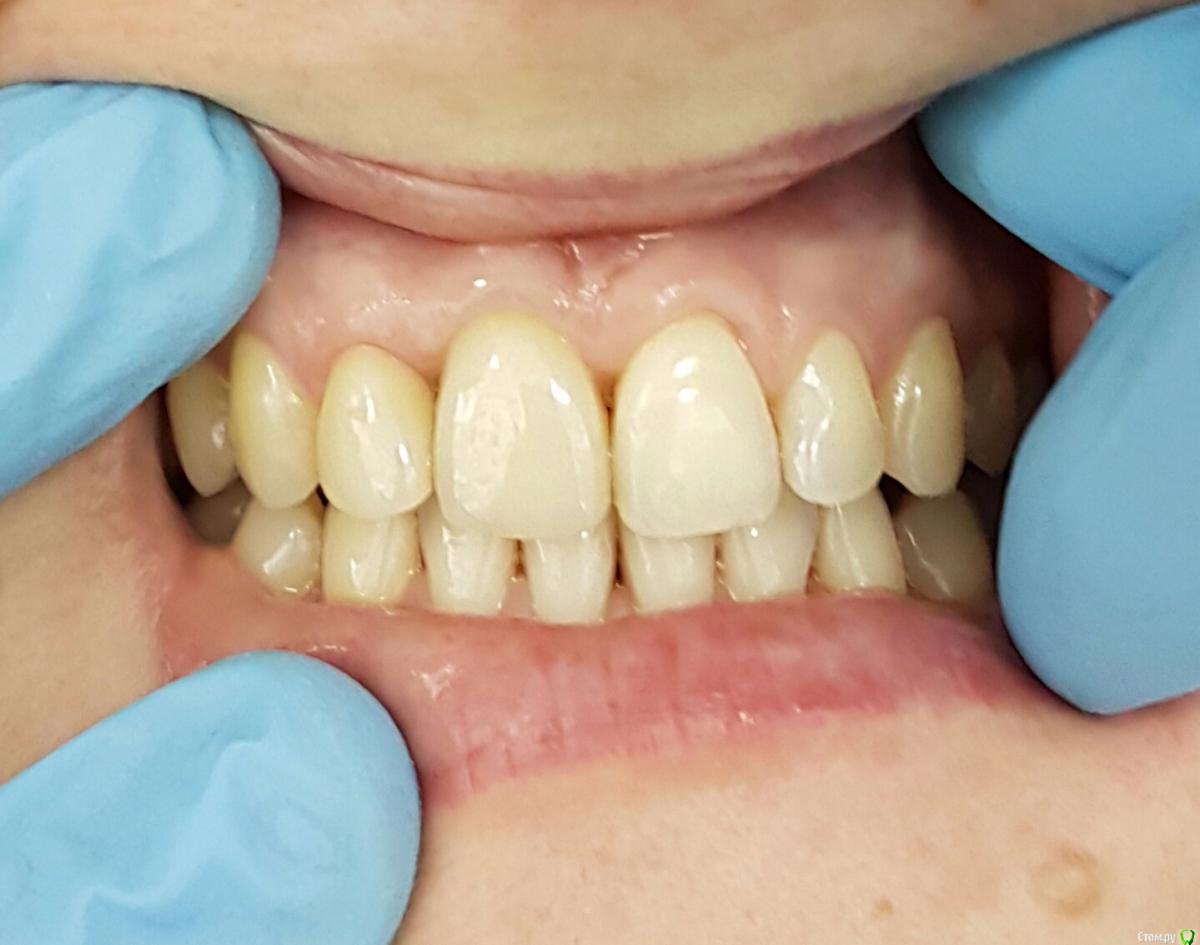

Kostoprav Опубликовано 8 июля, 2015 Автор Поделиться Опубликовано 8 июля, 2015 (изменено) продолжение истории) вот что было изначально а вот что получилось) временная реставрация она с ней до имплантации ходила, коронка на 12 тоже временная Изменено 8 июля, 2015 пользователем Kostoprav 3 Ссылка на комментарий

Kostoprav Опубликовано 9 марта, 2017 Автор Поделиться Опубликовано 9 марта, 2017 вот что получилось 9 Ссылка на комментарий